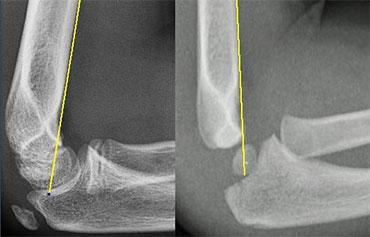

Có hai đường quan trọng giúp chẩn đoán trật khớp và gãy xương.

Đó là đường Quay-Chỏm (Radiocapitellar) và đường Cánh tay trước (Anterior humeral).

Đường quay-chỏm

Một đường kẻ qua trung tâm cổ xương quay phải đi qua trung tâm của chỏm con, bất kể tư thế của bệnh nhân như thế nào, vì xương quay khớp với chỏm con (hình minh họa).

Trong trường hợp trật xương quay, đường này sẽ không đi qua trung tâm của chỏm con.

Ở bên trái, chúng ta thấy rằng đường quay-chỏm đi qua trung tâm của chỏm con trên mọi phim X-quang, mặc dù C và D không ở tư thế chuẩn.

Lưu ý gãy xương trên lồi cầu ở hình B.

Bên trái là các ví dụ khác về đường thẳng quay-chỏm.

Hình ảnh phía dưới bên phải cho thấy sự trật khớp rõ ràng của xương quay.

Radiographs of elbows at different ages. The Anterior Humeral line goes through the middle third of the capitellum .

Đường Humeral trước.

Một đường kẻ trên phim chụp nghiêng dọc theo bề mặt trước của xương cánh tay phải đi qua một phần ba giữa của chỏm con.

Đường này được gọi là đường Humeral trước.

Trong các trường hợp gãy xương trên lồi cầu, đường Humeral trước thường đi qua một phần ba trước của chỏm con hoặc ở phía trước chỏm con do sự uốn cong ra sau của đoạn xương cánh tay xa.

Ở bên trái, đường thẳng cánh tay trước đi qua một phần ba trước của chỏm con.

Điều này cho thấy các lồi cầu bị di lệch về phía sau (tức là gãy trên lồi cầu).